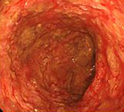

정확한 진단을 위해서는 여러 가지 검사를 병행해야 합니다. 병력을 듣고 진찰을 한 후 혈액검사와 함께 대장내시경검사로 장의 내부를 관찰합니다. 대장내시경 검사 시 직장을 침범하여 연속적으로 나타나는 점막의 부종, 혈관 소실, 궤양 등이 발견될 수 있습니다. 이때 반드시 조직검사를 시행해서 만성염증 소견을 확인해야 하며, 비슷한 내시경 소견을 보일 수 있는 몇 가지 질병과의 감별도 필요합니다.